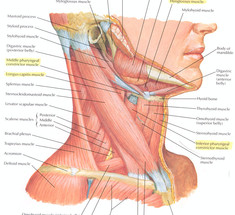

Избавляемся от дряблости шеи: омолаживающие упражнения

Экология здоровья и красоты. Упражнения этого комплекса препятствуют увяданию кожи шеи. Исходное положение...